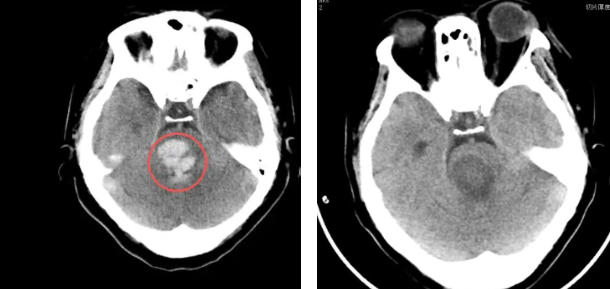

治疗前/治疗后(左图红圈内为出血区域)

患者女性,53岁,既往高血压病史20年余,入院前1小时无明显诱因出现意识不清,呼之不应,伴恶心、呕吐,家属急呼120送至我院急诊。头部CT扫描显示:脑干出血10.6ml,并溃入第四脑室,诊断为脑干出血、脑室出血。